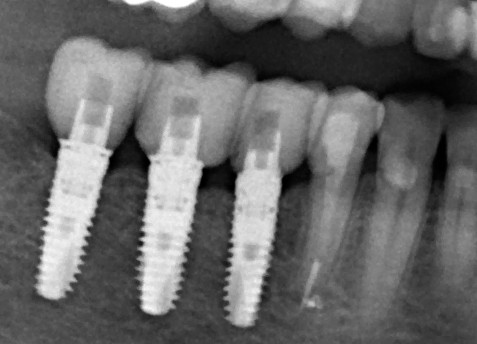

Так вот, чрезмерная атрофия альвеолярного гребня может лишить нас возможности имплантации — нам просто не хватит объемов костной ткани для нормальной установки имплантов. Однако, эта проблема решаема — существует целый ряд методик остеопластики (включая синуслифтинг), позволяющих восстановить любой объем костной ткани в в любом участке зубного ряда с высокой степенью эффективности. И, как правило, хорошие врачи в хороших клиниках так и поступают: